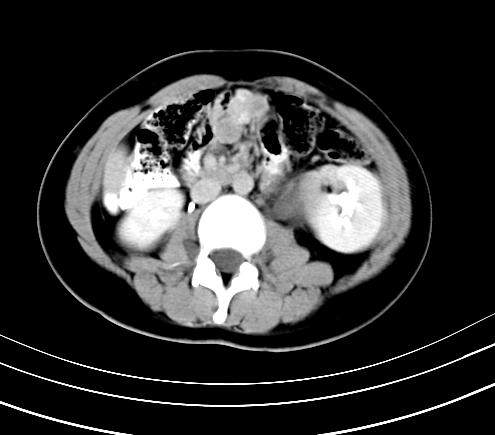

腹部平扫